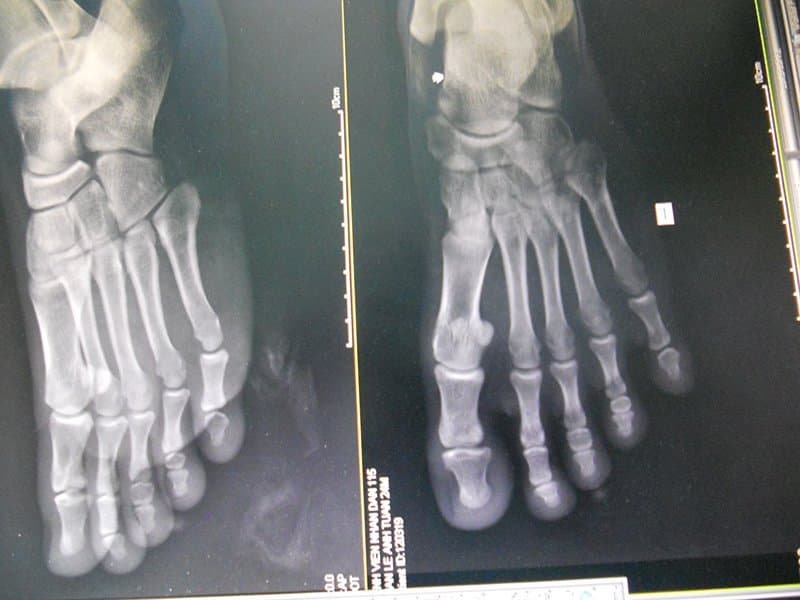

Các chấn thương tại bàn chân gây đau đớn và khó khăn trong sinh hoạt của người bệnh. Để chẩn đoán chính xác tình trạng Chấn thương tại bàn chân, bác sĩ chuyên khoa sẽ chỉ định người bệnh đi chụp X-quang bàn chân thẳng nghiêng để đưa ra chẩn đoán cuối cùng.

Chụp x-quang là phương pháp hữu hiệu giúp bác sĩ chẩn đoán chính xác và nhanh nhất tình trạng bệnh lý giúp kịp thời đưa ra các phương án chữa trị.

Sau khi có kết quả, phim chụp xương bàn chân phải đạt được các yêu cầu như sau:

- Lấy được các xương bàn chân bên cần chụp vào giữa phim

- Các xương bàn chân không chồng lên nhau.

- Phim có độ nét tương phản, phim sạch không bị xước.

- Có họ tên bệnh nhân, dấu P và T, ngày tháng năm chụp.